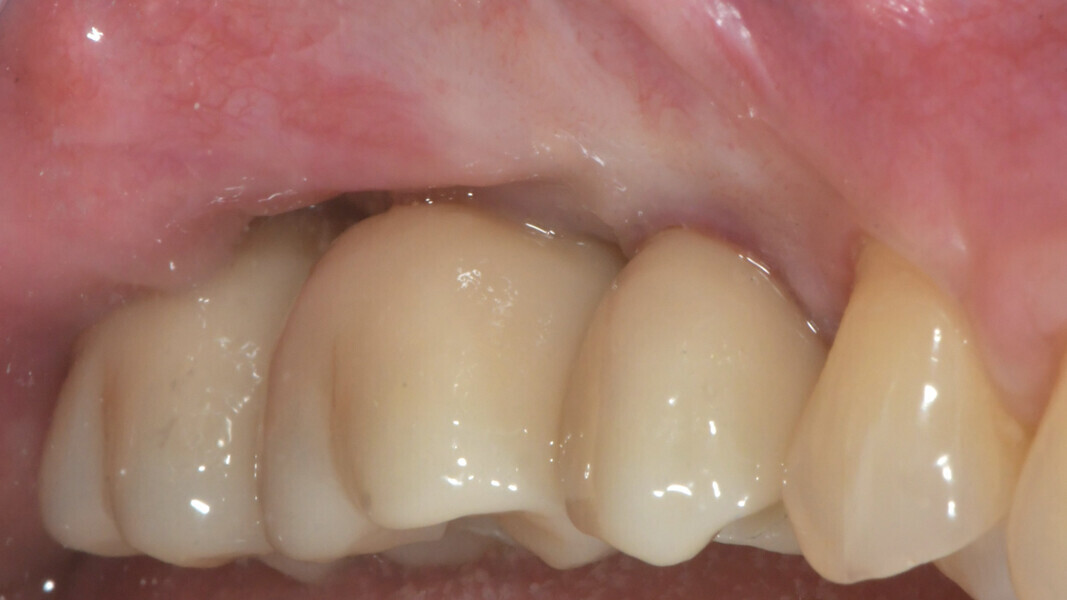

After three months, the implants were exposed through an apically positioned flap to increase the amount of keratinised tissue on the vestibular side of the implants and to realign the mucogingival junction, previously shifted towards the palate. Flared healing screws were placed to promote proper transmucosal healing. After one month, single ceramic crowns were placed for the first functional loading and temporary restoration while waiting for complete bone maturation (Fig. 34). After six months, the crowns were replaced with zirconia crowns for the final functional loading and the definitive restoration (Figs. 35–38). Clinical and radiographic follow-ups at the first functional loading, at six months, 12 months and 24 months showed the health of the peri-implant tissue and the maintenance of peri-implant bone levels (Figs. 39a-d).